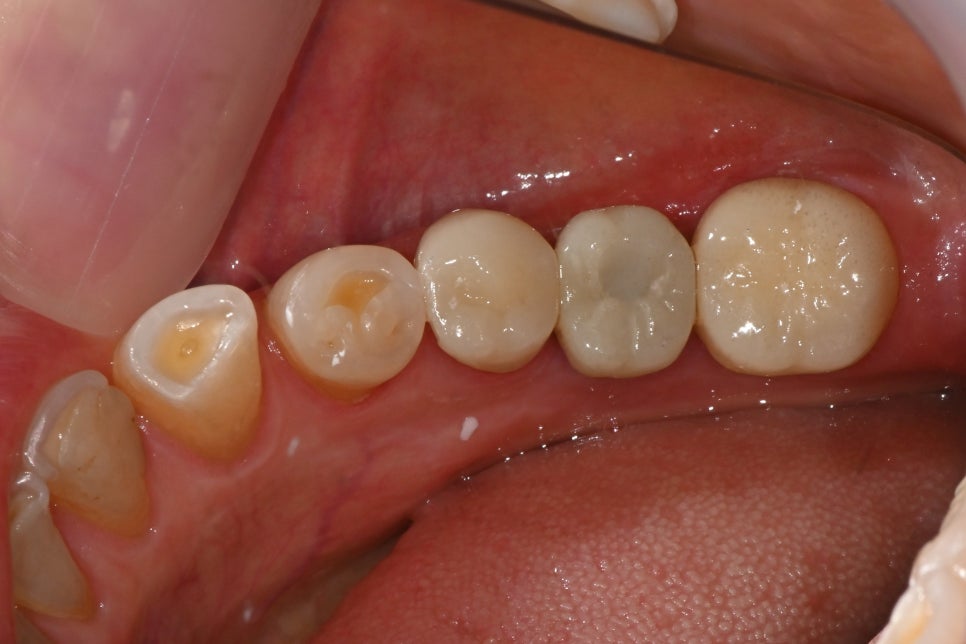

This shows the implant placed in the molar area and the crowns completed afterward. With colors and shapes harmonious with the natural teeth, both function and aesthetics were restored.

Intraoral photo after molar implant placement and prosthetic completion

"This is the appearance of the front tooth crowns, completed in harmony and aesthetics like natural teeth, and the implant prosthetics that restored function."